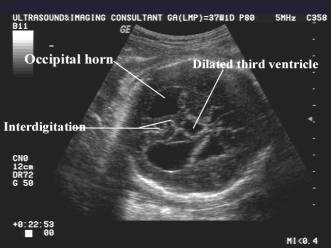

Interhemispheric cyst,high-riding 3rd ventricle |

Colpocephaly |

Interhemispheric fissure adjoins the 3rd ventricle |

Colpocephaly (dilatation of the occipital horn of the

lateral ventricle). |

o

Absence

of the cavum septi pellucidi, upward displacement and enlargement of the third

ventricle

Enlarged

occipital horns (colpocephaly) of the lateral ventricles,

separated

and enlarged anterior horns,

interhemispheric spaces are the key indirect signs of CACC.